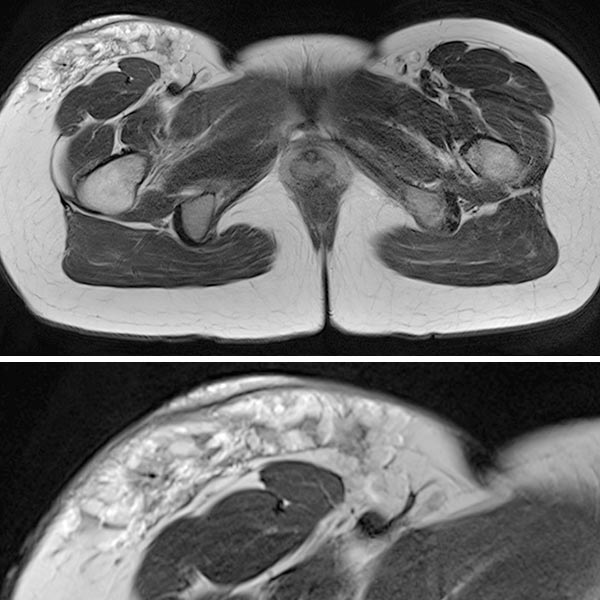

In der transversalen T2-Wichtung, fettunterdrückt, ist die rein epifasziale Ausdehnung der LM im subkutanen Fettgewebe klar zu erkennen. Die darunter liegende Muskulatur ist nicht betroffen.

Beachte in der Ausschnittsvergrößerung (unteres Bild) die exophytische Ausdehnung der mikrozystischen Anteile (stark hyperintens) der LM bis über das Niveau der Haut.

In der gleichen Schichtführung der MRT (oben Übersicht, unten Ausschnittsvergrößerung) in T2-Wichtung ohne Fettunterdrückung sind die gleichzeitig vorhandenen bindegewebigen Anteile der hart tastbaren LM als hypointense netzartige Zeichnung besser zu sehen. Beachte wieder den erhabenen exophytischen Anteil oberhalb des Hautniveaus.

In der axialen fettunterdrückten T1-Wichtung nach KM-Gabe (oben Übersicht, unten Ausschnitt) findet sich die stärkste Anreicherung in den kutan gelegenen, expophytischen, mikrozystischen Anteilen in der Haut. Die darunter liegende LM im subkutanen Fettgewebe reichert dagegen kaum an.